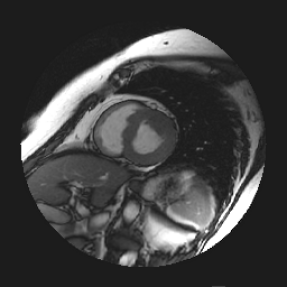

Quantitative evaluation was performed on the test set by registering image slices at ED to ES, and vice versa, which resulted in 258 independent registration experiments. The obtained transformation parameters were used to warp the left ventricle annotations of the moving image to the fixed image. The transformed annotations were compared with the reference annotations in the fixed images. The results are listed in Table 1. The best registration results were obtained with the DIRNet-C1 on an NVIDIA Titan X Maxwell GPU in s. For comparison, the table also lists conventional iterative intensity-based registrations (SimpleElastix), with parameters specifically tuned for this task. SimpleElastix used a similar grid spacing as the DIRNet but with a multiresolution approach, downsampling first with a factor of 2 and thereafter using the original resolution. Updating in 100 iterations per resolution was sufficient for convergence with a reasonable time span. Experiments were performed with an Intel Xeon 1620-v3 3.5 GHz CPU using 8 threads in s (10 times slower than the DIRNet). Figure 4 shows registration results for a randomly chosen image pair.

| Fixed image | Moving image | DIRNet | SimpleElastix |

|---|---|---|---|

![]() |

5 Discussion and Conclusion